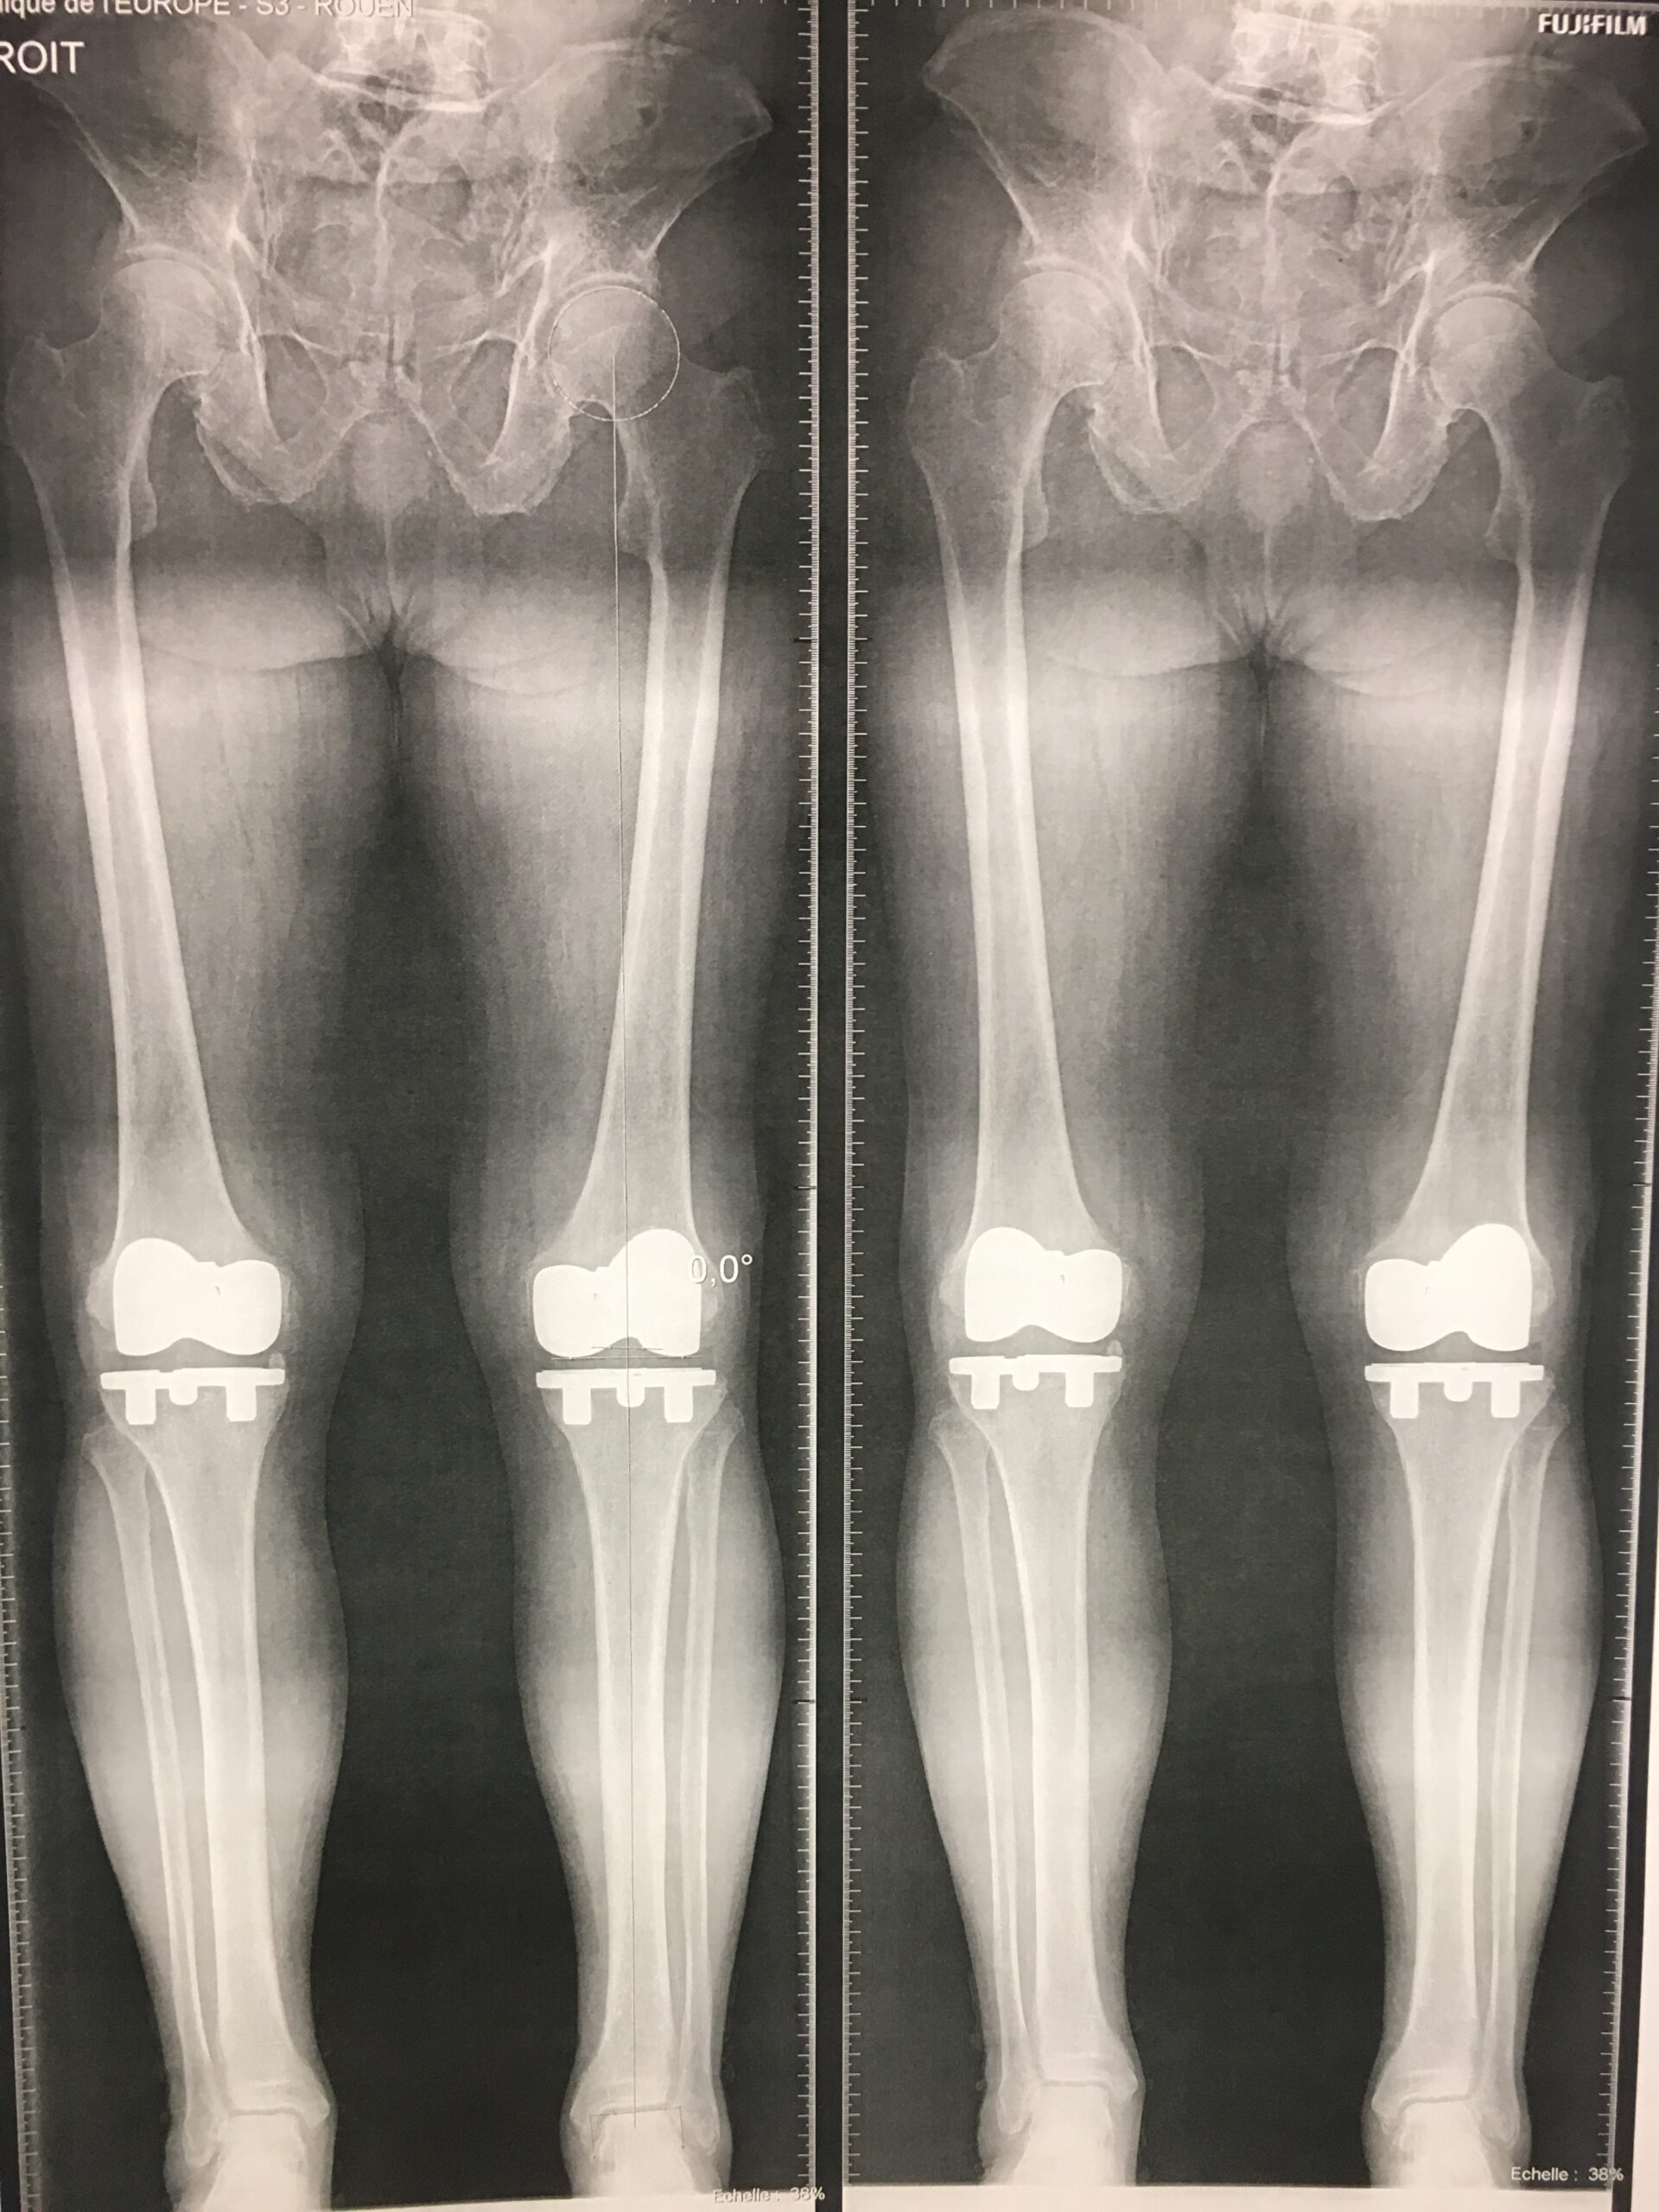

Chirurgie avec assistance robotisée de type Mako Stryker

Dr. Julien Synave est un chirurgien orthopédiste reconnu, spécialisé dans le traitement des pathologies complexes du genou, des articulations, ainsi que des membres inférieurs et supérieurs. Avec son expérience de plus de 30 ans, il vous proposera des solutions personnalisées pour soulager vos douleurs articulaires et améliorer votre mobilité.